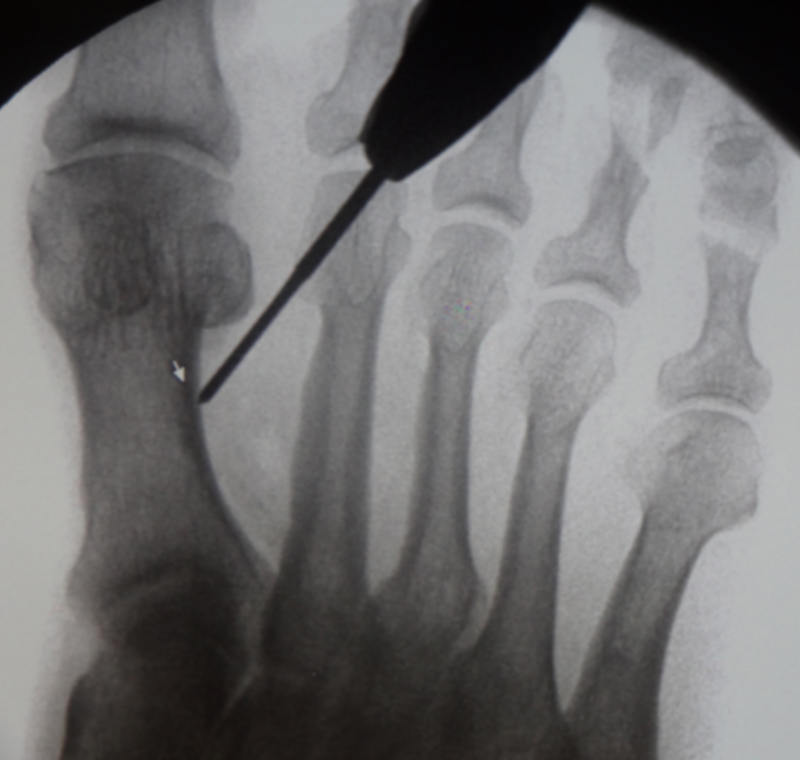

• Bildverstärker für intraoperative Kontrollaufnahmen 3.

• Bildverstärker.

• Positionierung des Bildverstärkers im 90° Winkel zur Fußlängsachse (Abbildung 4).

Die Fräse wird auf eine Drehzahl von 3000 – 5000 RPM eingestellt.